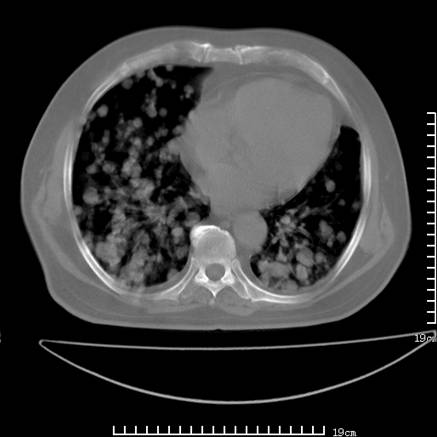

张男,75岁,干咳半年余,小便不利二年,b超检查前列腺增大,未见明显肿块;前列腺癌血生化检查多项指标明显增高。

双肺内多发转移瘤,纵膈淋巴结转移。来源前列腺?建议盆腔mri进一步检查。

双肺转移满了。

两肺广泛转移瘤。